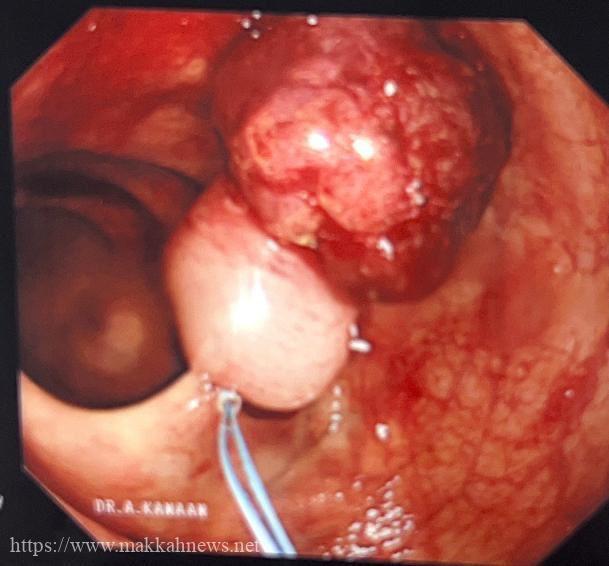

اوضح إستشاري ورئيس قسم الجهاز الهضمي والمناظير والكبد الدكتور عبدالرحمن كنعان الذي اجرى عملية المنظار ” حضر المريض للعيادات الخارجية وهو يعاني من نقص حاد في الدم مع وجود دم مخفي في البراز وتم عمل الفحوصات اللازمة مما أستدعى تنويم المريض لعمل منظار للجهاز الهضمي السفلي حيث تبين وجود ورم يبلغ حجمه 4×3 سم والاخر 5×6 سم .

وبعد أخذ العينه أتضح بأن الأورام حميدة وقابلة للتحول تم إجراء عملية المنظار استغرقت 45 دقيقه من خلالها تم إستئصال الورم بواسطة تقنية Endo loop دون الحاجة للتدخل الجراحي